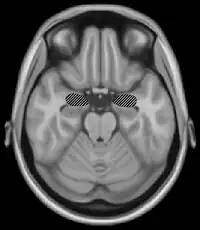

Basal ganglia (red) and related structures (blue)

The basal ganglia are a group of nuclei which are located in the medial temporal lobe, above the thalamus and connected to the cerebral cortex. Specifically, the basal ganglia includes the subthalamic nucleus, substantia nigra, the globus pallidus, the ventral striatum and the dorsal striatum, which consists of the putamen and the caudate nucleus.[8] The basic functions of these nuclei deal with cognition, learning, and motor control and activities. The basal ganglia are also associated with learning, memory, and unconscious memory processes, such as motor skills and implicit memory.[4] Particularly, one division within the ventral striatum, the nucleus accumbens core, is involved in the consolidation, retrieval and reconsolidation of drug memory.[9]